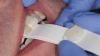

After centric relation is found, the point of first contact must be determined. The point of first contact may be a keystone tooth, but not everyone has a keystone tooth. The point of first contact needs to be marked, but not necessarily physically. In Figure 1, showing teeth Nos. 2 and 3, the point of first contact is on the mesiolingual cusp of No. 2, which has the strongest blue mark. There is also a slight mark on the distal buccal cusp of tooth No. 3. When the jaw is in centric relation, the point or coincident points of first contact are called centric occlusion. Centric relation is a joint position and is found independent of tooth contact; the joint is centered and teeth do not need to touch if centric relation is in the joint space. When the opposing teeth come together in the joint space, the term is centric occlusion.1

Fig 1. Point of first contact.

Figure 1